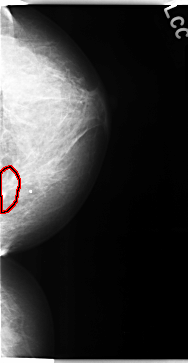

C_0107_1.LEFT_CC

FILE: C_0107_1.LEFT_CC.OVERLAY

TOTAL_ABNORMALITIES 1

ABNORMALITY 1

LESION_TYPE MASS SHAPE OVAL MARGINS ILL_DEFINED

ASSESSMENT 5

SUBTLETY 2

PATHOLOGY MALIGNANT

TOTAL_OUTLINES 1

BOUNDARY